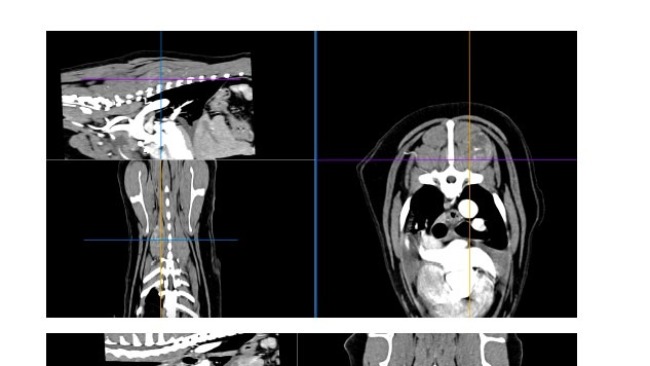

Zwykłe badanie profilaktyczne, a wyszło: podniesiony kortyzol, powiększone węzły chłonne, pobudzona śledziona i płyn w jamie opłucnowej.

Badania moczu, badanie krwi, USG jamy brzusznej, echo serca, rtg, wizyta onkologiczna.... To wszystko co już mamy za sobą i nadal nie wiadomo co się z Atenką dzieje i nie wiadomo jak ją leczyć. Wykluczony został zespół Cushinga. Wykluczone zostały choroby serca. Podejrzenie chłoniaka na razie nie zostało potwierdzone. Diagnostyka trwa dalej, a koszty rosną w przerażającym tempie. Przed nami tomografia oraz biopsja śledziony, biopsje węzłów chłonnych, badanie cytologiczne płynu z jamy opłucnej. To koszt minimum 3000 zł.